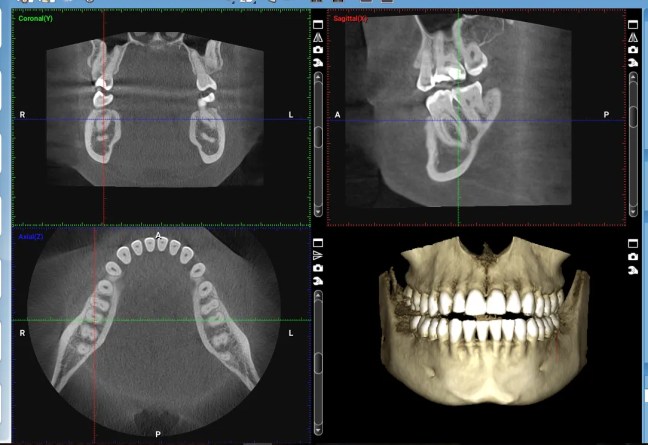

Milyen típusú fogászati CBCT felvételek léteznek – és mikor van rájuk szükség? Érdemes CT felvételt készíttetni fogorvosi vizsgálat előtt?

https://videopress.com/v/YUfjT4fi?resizeToParent=true&cover=true&autoPlay=true&controls=false&loop=true&muted=true&persistVolume=false&playsinline=true&posterUrl=https%3A%2F%2Fvideos.files.wordpress.com%2FYUfjT4fi%2F1000035911_mp4_std.original.jpg&preloadContent=metadata&useAverageColor=true A CBCT (kúpsugaras CT) egy speciális, 3D-s képalkotó eljárás, amely sokkal részletesebb képet ad a fogakról, az állcsontokról és a környező területekről, mint a hagyományos röntgen. De nem minden CBCT egyforma – attól függően, hogy mit kell vizsgálni, többféle felvétel létezik.1. Kis területű felvétel – ha egyetlen fog a kérdésEz a típus csak egy … Milyen típusú fogászati CBCT felvételek léteznek – és mikor van rájuk szükség? Érdemes CT felvételt készíttetni fogorvosi vizsgálat előtt? részletei...